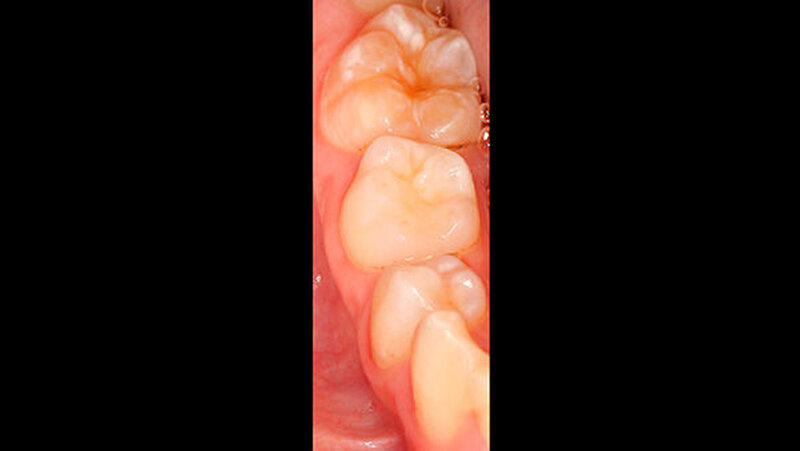

Der vor wenigen Jahren extrahierte Molar war der 16, anschließend war es im Laufe der Zeit im ersten Quadranten zu einer verhältnismäßig gleichmäßigen Lückenbildung gekommen. Der Zahn 17 war weitestgehend aufgewandert (Abbildung 2). Zahn 26 (Abbildung 3) wies eine umfangreiche adhäsive Restauration okklusal-bukkal auf. Zusätzlich dazu gab es aber auch weitere Areale mit veränderter Opazität von milchig-weiß (insbesondere palatinal) bis gelb-braun.